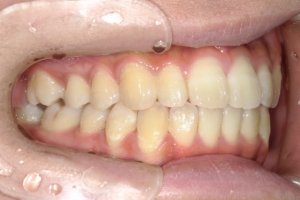

PROCESS

半年

AFTER

治療後

下の前歯が上あごの歯ぐきに当たるほど噛み合わせが深く、そのことが原因で上顎歯列の正中にすき間(正中離開)が生じていました。部分矯正ですき間を無理やり閉じても、噛み合わせが深いままでは治療後の再発リスクが高くなります。そのため全体矯正で奥歯の噛み合わせを整え、噛み合わせを浅くしつつ前歯を並べました。正中離開は戻りやすい傾向があるので、再発を防ぐため固定式リテーナーを推奨しています。